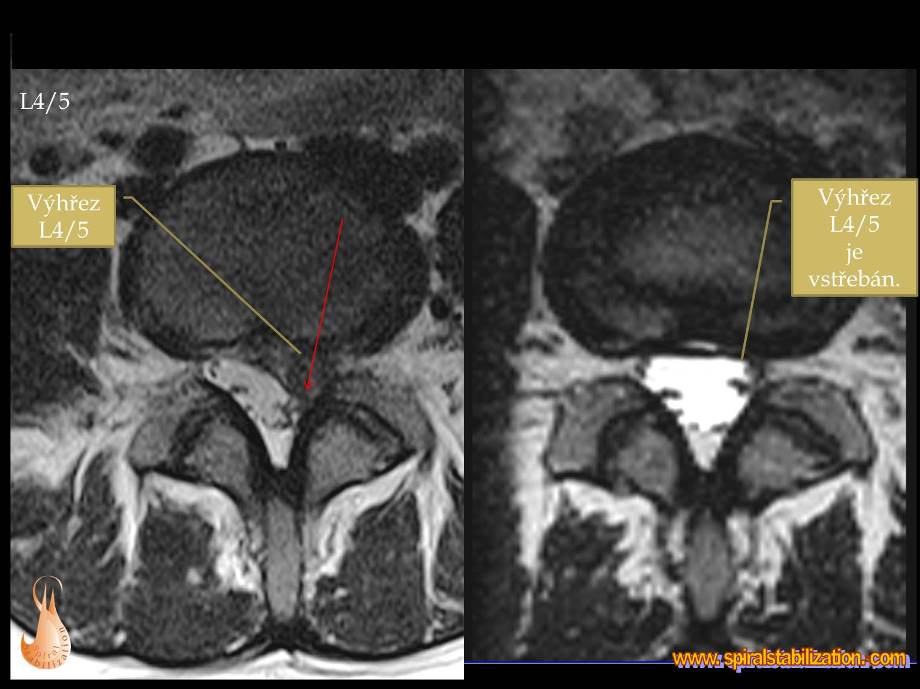

Výsledky hernia L4/L5